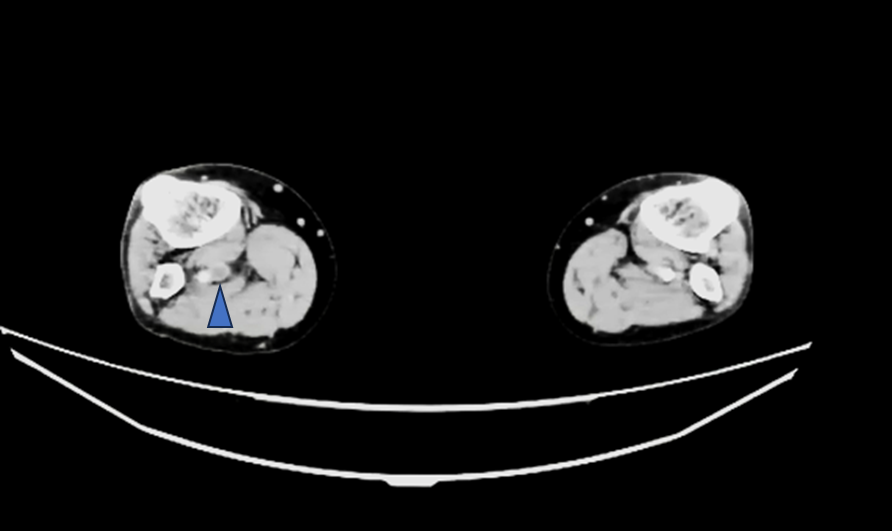

この方は検査前情報にはなかったのですが、右のTKA術後の方でした。右膝関節術部周囲を主体に下腿~大腿骨遠位レベルにfilling defectが複数認められました。

管電圧を下げて撮影することで、造影剤が60mlほどでも深部静脈の評価が可能でした。時間経過で造影効果が低くなった肺動脈の観察も観察することができました。

造影後”15分後”に追加で撮影した画像がこちらです。

造影後15分後でも造影効果がわずかに残っていました。

これを見ると、冠動脈CTでは右肺動脈に大きい血栓があるように見えましたが、左肺動脈の方が血栓サイズが大きく、これによる左胸の痛み症状だったのではないかと考えられました。

下肢静脈も15分後でもわずかに造影効果が残っており、左浅大腿静脈にfilling defectを認めました。

造影剤量も60mlと通常の深部静脈を観察するには少ない量でしたが、15分後の撮影でもなんとか観察することができました。

こちらも管電圧を下げて撮影しました。時間経過で造影効果が低くなった肺動脈や深部静脈の造影効果を上げてなんとか観察することができた症例です。